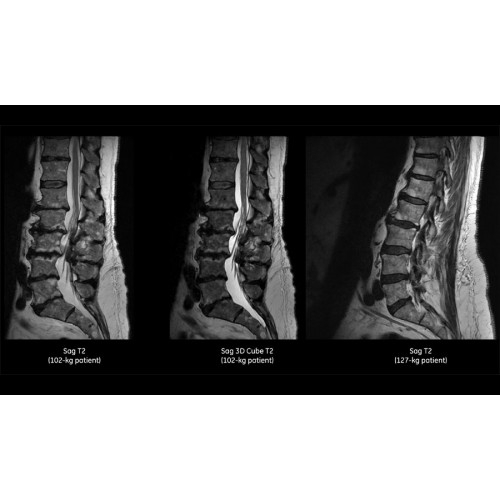

Система SIGNA Pioneer воплощает поразительные достижения в области визуализации. Передовая технология Total Digital Imaging (TDI) позволяет добиться большей четкости изображений и на четверть повысить соотношение сигнал/шум.

• Технология Digital Surround Technology (DST) — это новая технология объемной оцифровки данных, объединяющая сигналы от каждого элемента катушки. Прекрасное соотношение сигнал/шум и чувствительность поверхностных катушек в сочетании с превосходной однородностью и высокой проникающей способностью встроенной радиочастотной катушки — все это позволяет создавать качественные изображения не только позвоночника, но и всего тела.